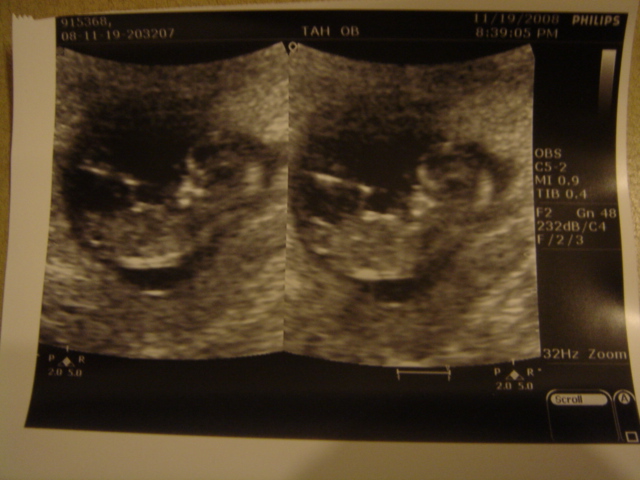

這次照的是胎兒頸部透明帶檢查(需自費1,000元)

測量目的在於輔助唐氏症篩檢 除了篩檢胎兒染色體異常

還可以於產前篩檢出許多畸形症狀和先天性心臟病

適合檢查時間為懷孕11-14週

之前看到的小bb都是一個小小圓圓的樣子

但這次看到他 真得很不一樣了

他不在是個胚胎 而是貨真價實的胎兒了

當護士小姐一壓我的肚子

他就動個不停 一下子動動手 一下子動動腳 超可愛的啦~

好神奇喔~ 太感動了~